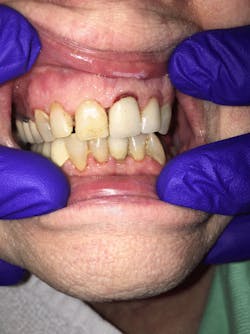

Figure 1: No. 2 prior to the Riva Star application

Figure 2: No. 2 after the application of Riva Star silver diamine fluoride and potassium iodide solution. Note the creamy white precipitate from the potassium iodide solution.